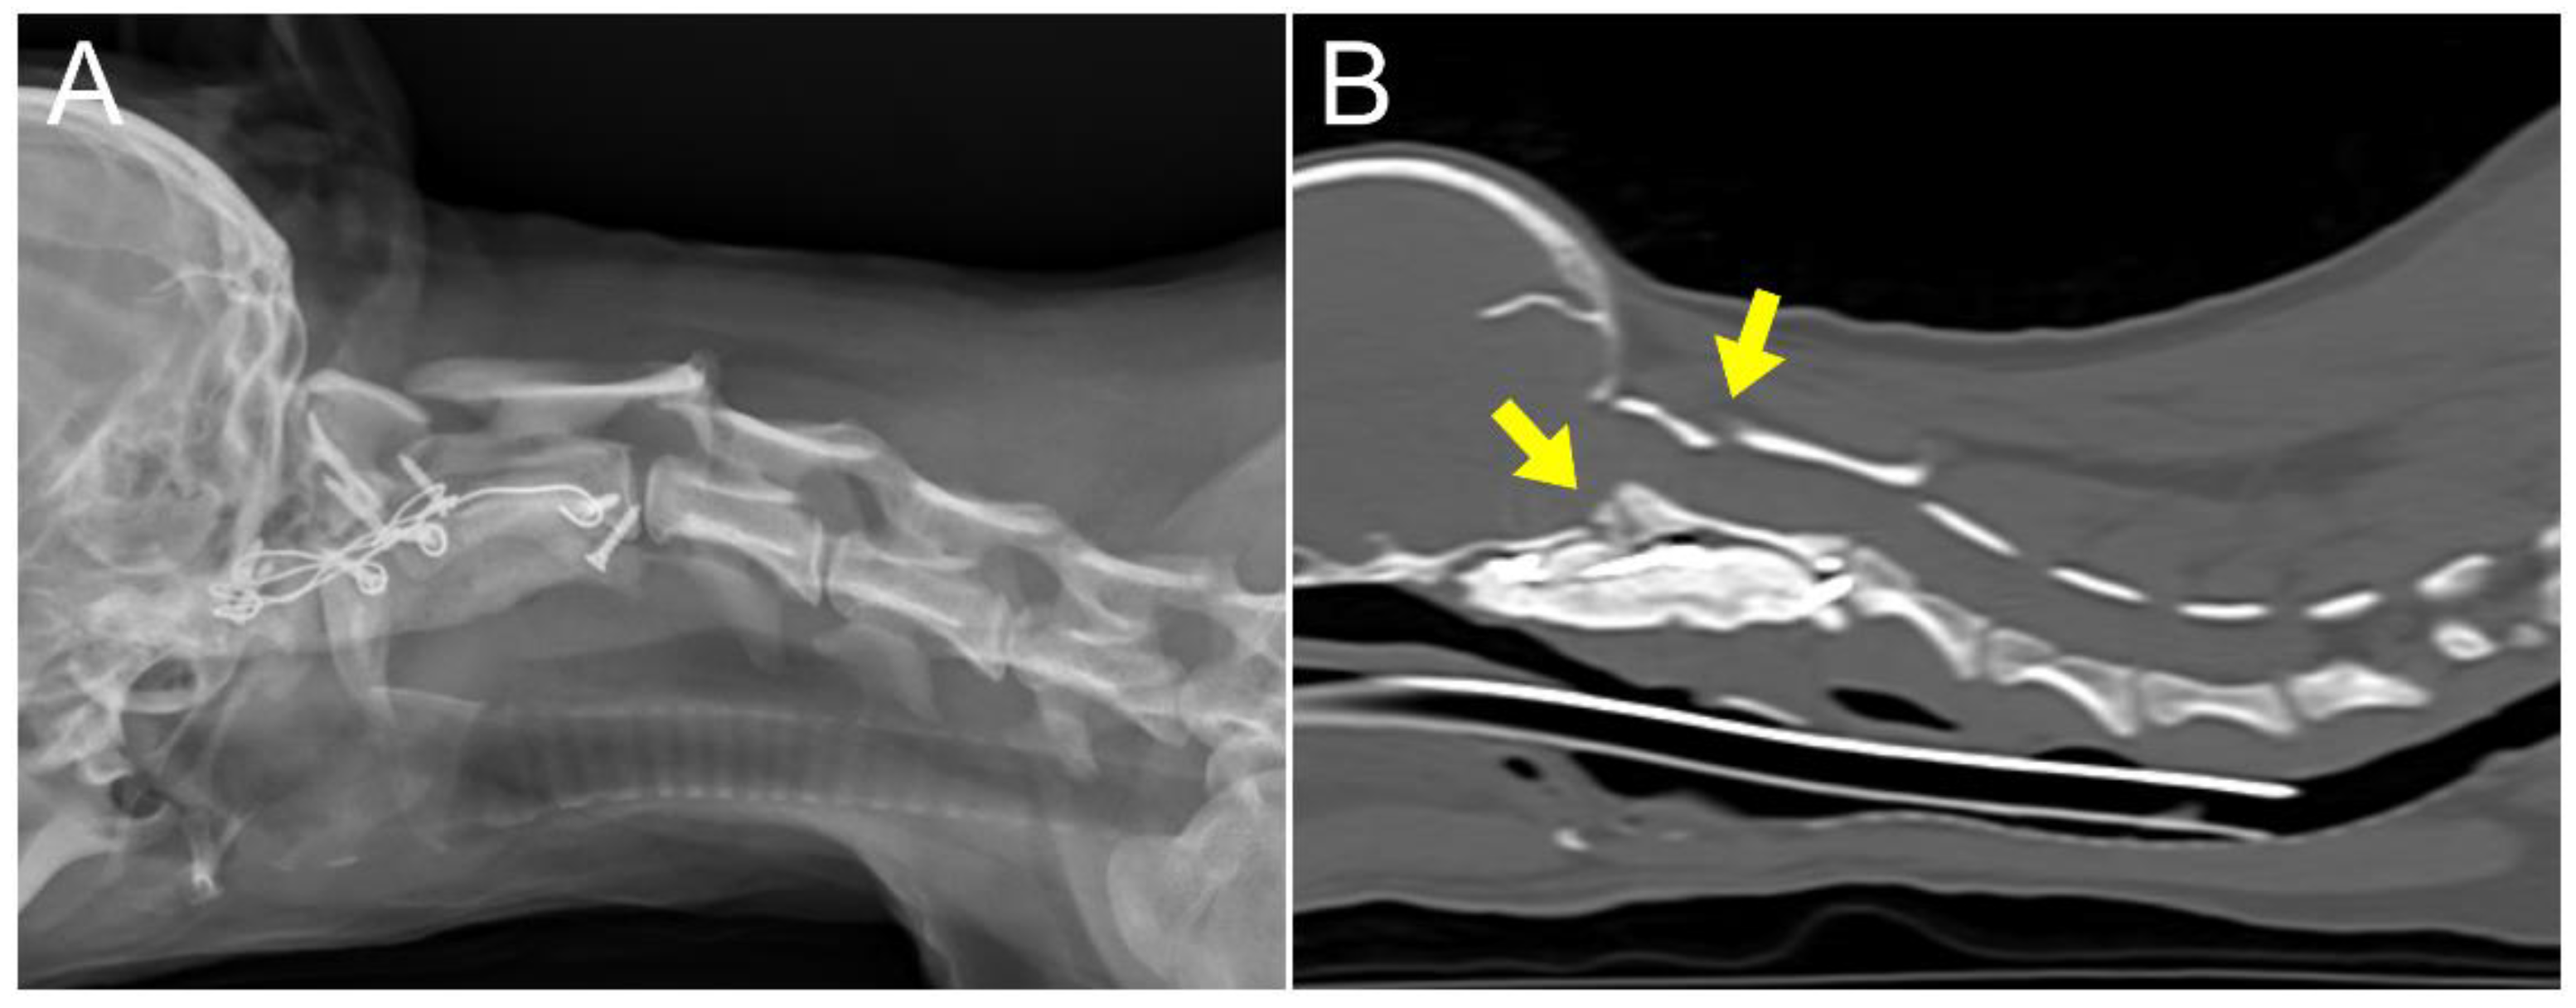

2. Case Description